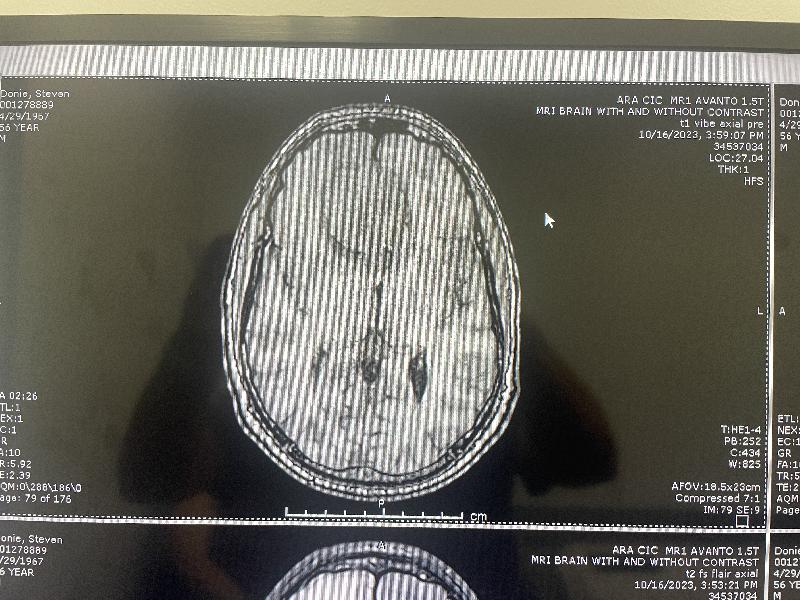

MRI, top view